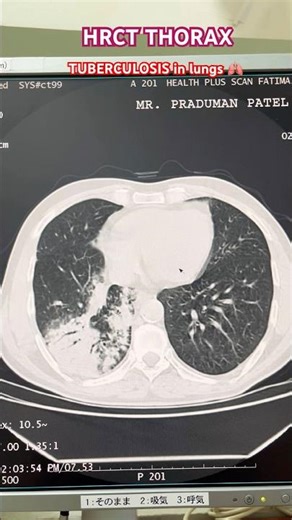

- CT

YouTube - CT Scan